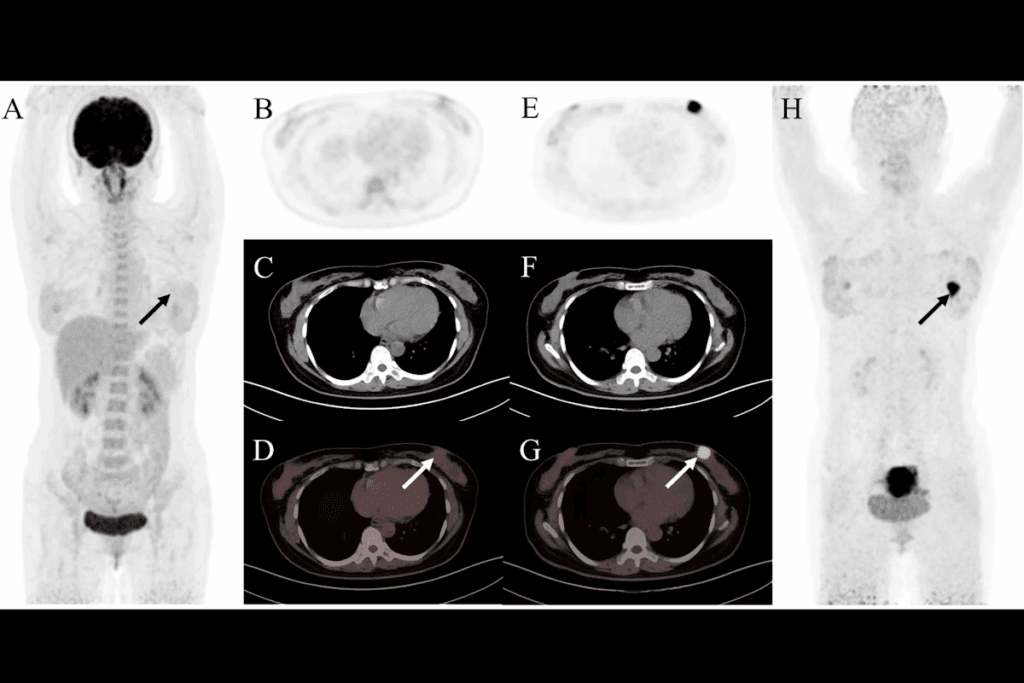

Real-Time CT Guidance Techniques

We use real-time CT guidance throughout the procedure. This means we get continuous CT scans. These scans show us where the needle is in relation to the tissue.

This feedback lets us make precise adjustments. It ensures we get the tissue sample from the right spot.